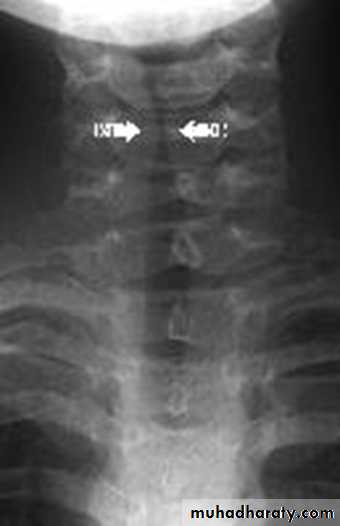

Investigation:

Anteroposterior X-ray of the neck shows subglottic narrowing (steeple sign).